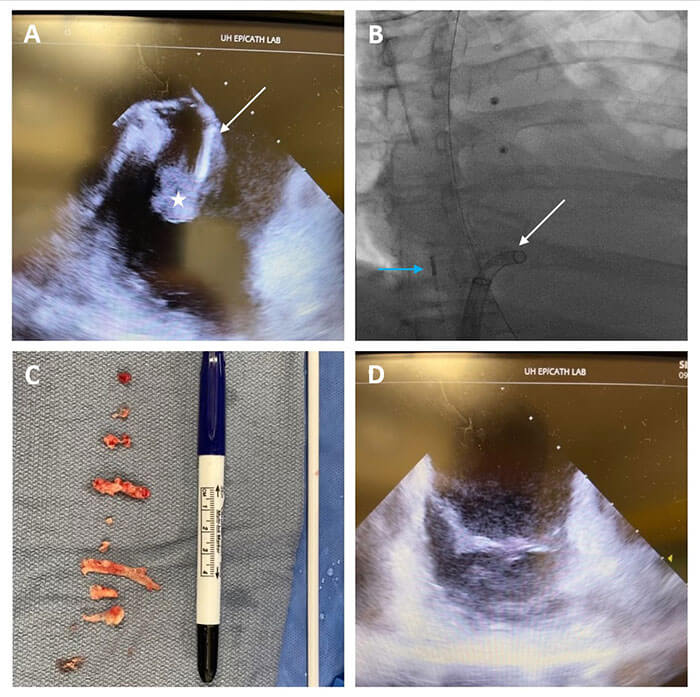

Endocarditis imagePanels A and B show ICE (blue arrow)-guided percutaneous removal of a large tricuspid valve vegetation (white star) using the Triever aspiration system (white arrow). Vegetation was removed outside the body (Panel C) and repeat ICE confirmed minimal residual valve vegetation (Panel D).